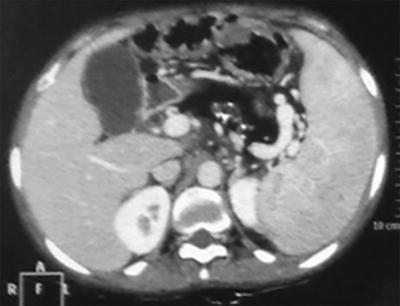

Image

Axial contrast-enhanced computed tomography (CECT) image showing short truncated pancreas with the absence of body and tail of pancreas. Small intestinal loops are seen in the pancreatic bed suggestive of dorsal pancreatic agenesis.